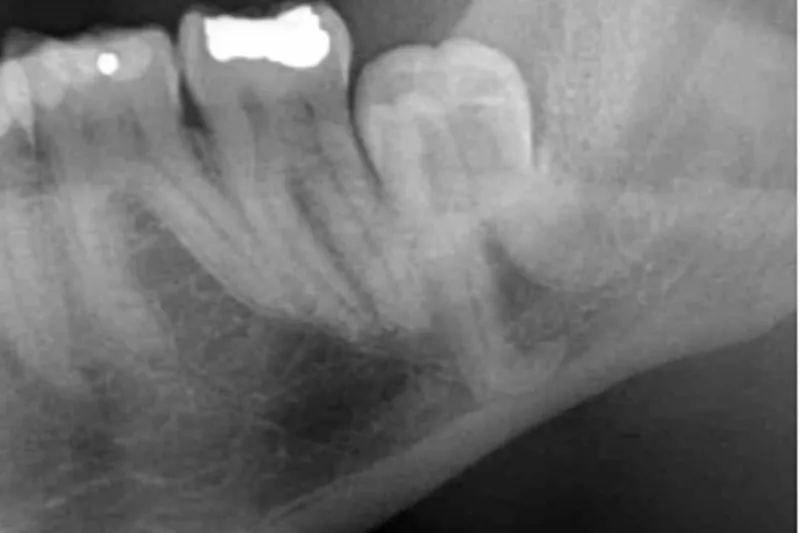

Kirurgisk fjernelse af mandiblens tredjemolar (M3) er almindeligvis forbundet med postoperative gener af ca. en uges varighed. Imidlertid kan patientrelaterede, anatomiske, patologiske og kirurgiske risikofaktorer indvirke på varigheden og graden af de postoperative gener. Patientens oplevelse af behandlingen og livskvaliteten umiddelbart efter operationen påvirkes ved svære postoperative gener. Stigende alder, rygning, overvægt, kompromitteret immunrespons, præoperativ dårlig mundhygiejne, smerter og infektion omkring M3, pericoronitis, menstruationscyklus, tandens impaktering og vinkling i mandiblen, operationsvarigheden og mindre kirurgisk erfaring er kendte risikofaktorer, som kan forværre varigheden og graden af generne efter kirurgisk fjernelse af M3. Kendskab til de forskellige risikofaktorer og deres indflydelse på de postoperative gener er derfor vigtigt for at bedre patienttilfredsheden. Forskellige informative, profylaktiske og farmakologiske foranstaltninger kan derfor anvendes med det formål at reducere varigheden og graden af de postoperative gener. Nærværende artikel har til formål at beskrive den nuværende viden om de forskellige patientrelaterede, anatomiske, patologiske og kirurgiske risikofaktorers indvirkning på varigheden og graden af de postoperative gener efter kirurgisk fjernelse af M3 inklusive anbefalinger til bedring af patienttilfredsheden og livskvaliteten efter behandlingen.

Surgical removal of the mandibular third molar (M3) is commonly associated with postoperative discomfort for approximately one week. However, patient-related, anatomical, pathological, and surgical factors may affect the duration and degree of postoperative discomfort. Patients perception of the treatment and the quality of life immediately after surgery is influenced by severe postoperative discomfort. Increasing age, smoking, obesity, compromised immune response, preoperative poor oral hygiene, pain and infection around the third molar, pericoronitis, menstrual cycle, impaction and angulation of the third molar, duration of surgery, and less surgical experience are recognized risk factors that can exacerbate the duration and intensity of discomfort following surgical removal of M3. Understanding the various risk factors and their impact on the postoperative discomfort is essential to improve patient satisfaction. Utilizing various informative measures as well as prophylactic- and pharmacological tools can therefore be used to reduce the duration and intensity of postoperative discomfort. The objective of this article is to delineate the current understanding of patient-related, anatomical, pathological, and surgical risk factors. It also describes their influences on the duration and intensity of postoperative discomfort following surgical removal of M3, and includes recommendations for enhancing patient satisfaction and the overall quality of life.